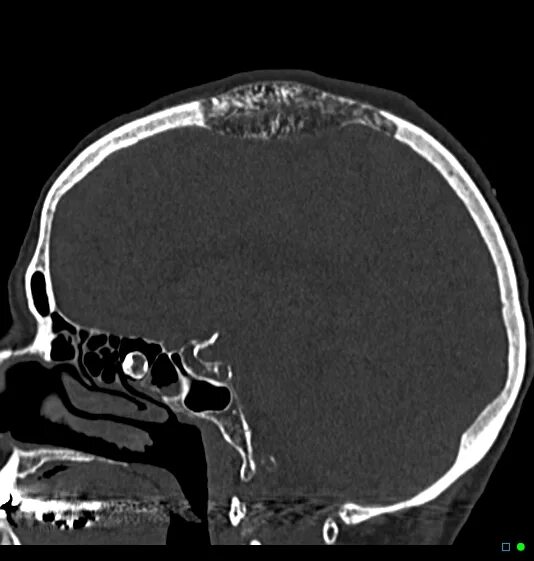

Череп на кт